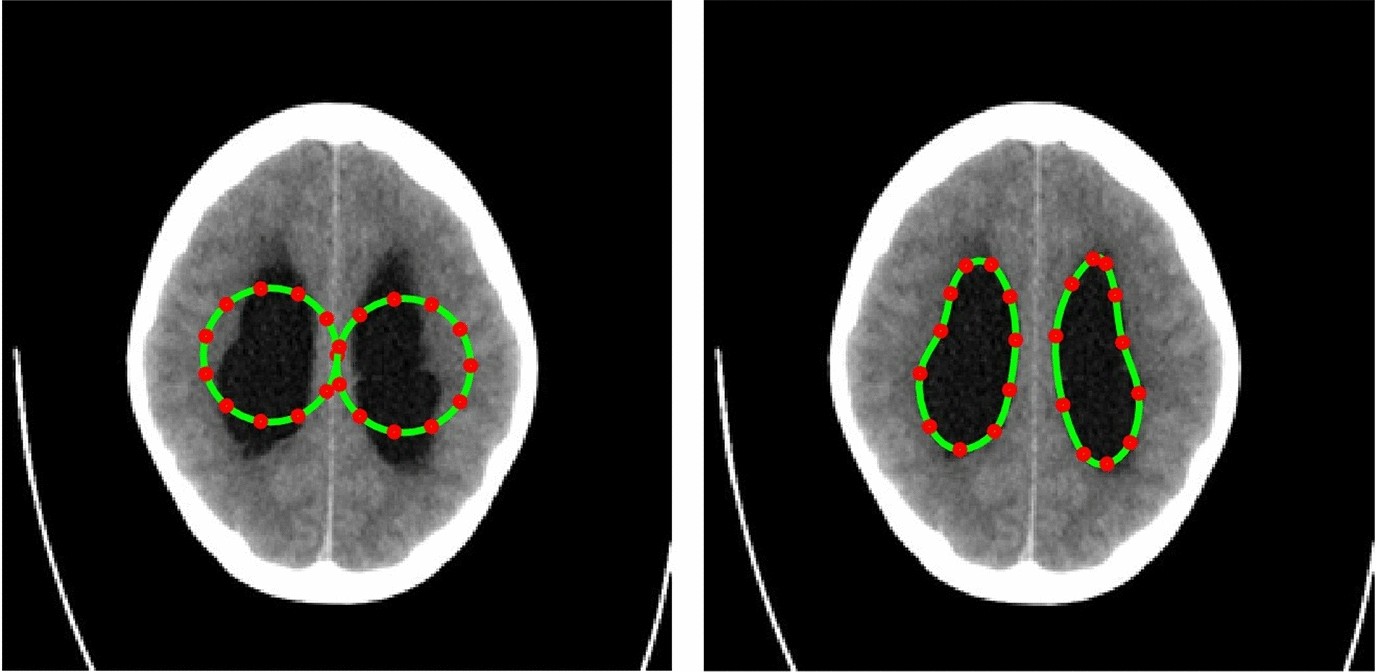

Segmentation of enlarged ventricles of a hydrocephalus patient. Left: Initial weights, Right: Optimized weights.